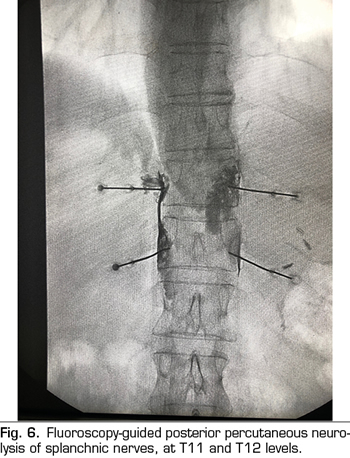

Percutaneous technique

The percutaneous technique is performed using a retrocrural posterior approach, usually guided by fluoroscopy (Figure 6). The lesions can be performed by conventional radiofrequency or using neurolytic agents as in the celiac plexus.